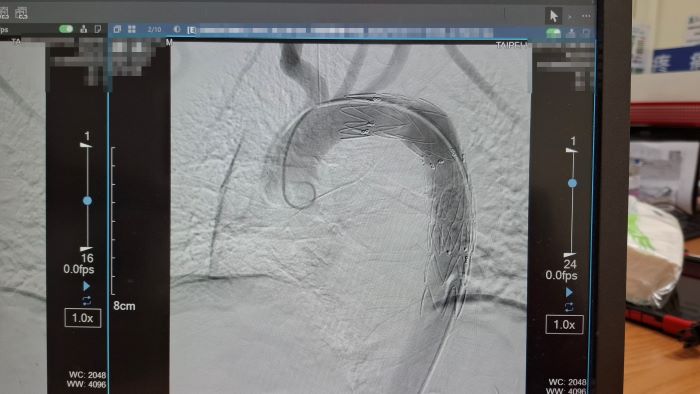

《圖說》孟繁傑醫師施以「胸主動脈支架置放手術」。〈臺北醫院提供〉

院方緊急會診心臟血管外科醫師孟繁傑,評估後立即施行「胸主動脈腔內血管支架置放手術」,僅在腹股溝處開出不到1公分的小傷口,將支架透過導管送入主動脈破裂處封堵出血點,成功解除致命危機。廖先生術後恢復順利,目前已平安出院。

孟繁傑表示,近年來,主動脈腔內血管支架置放手術逐漸成為主流治療方式。醫師只需從腹股溝股動脈置入導管,將金屬支架精準送到破裂位置撐開血管並封住破口,不僅傷口小、手術時間短,也能降低出血與併發症風險。目前此項治療方式已被美國血管外科學會列為主要治療建議,台灣健保也已納入給付,讓患者能以較低負擔接受先進治療。